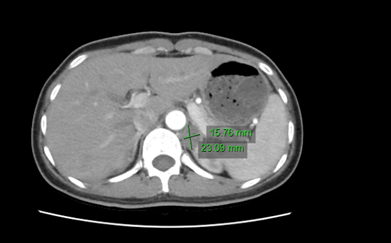

Qua thăm khám đánh giá, bệnh nhân được chỉ định thêm một số cận lâm sàng, kết quả: hormon vỏ thượng thận (aldosteron) tăng rất cao trong máu, renin máu giảm rất thấp, chụp cắt lớp ổ bụng cho thấy hình ảnh u thượng thận trái kích thước 15 x 20 mm. Bệnh nhân được chẩn đoán Hội chứng Conn hay còn gọi là khối u thượng thận sản sinh aldosteron gây nên cao huyết áp thứ phát. Bệnh nhân được hạ áp bằng amlor, bù kali và chuyển khoa Ngoại tổng hợp, Bệnh viện đa khoa Quốc tế Hải Phòng mổ cắt bỏ tuyến thượng thận trái. Sau mổ, huyết áp bệnh nhân và kali máu trở về bình thường mặc dù không sử dụng thuốc huyết áp và không bù kali.